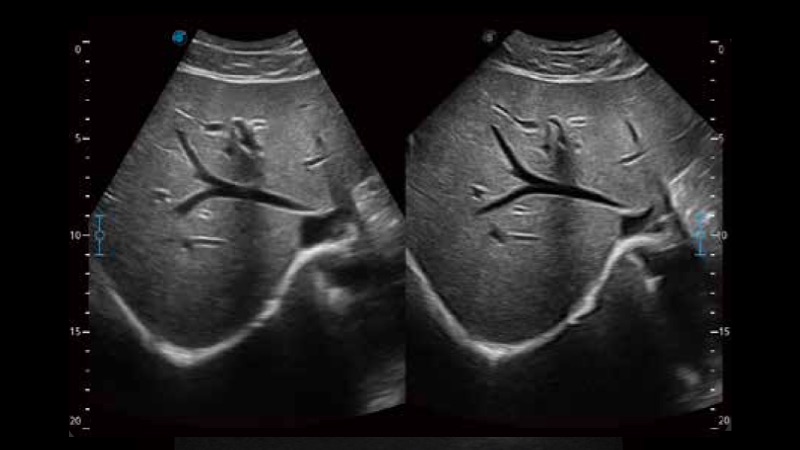

μ-Scan+新一代微米成像技术

新一代微米成像技术大大提高了器官和病变的可见性。高清对比度分辨率将抑制斑点噪声,同时保持真实的组织结构。

临床图像